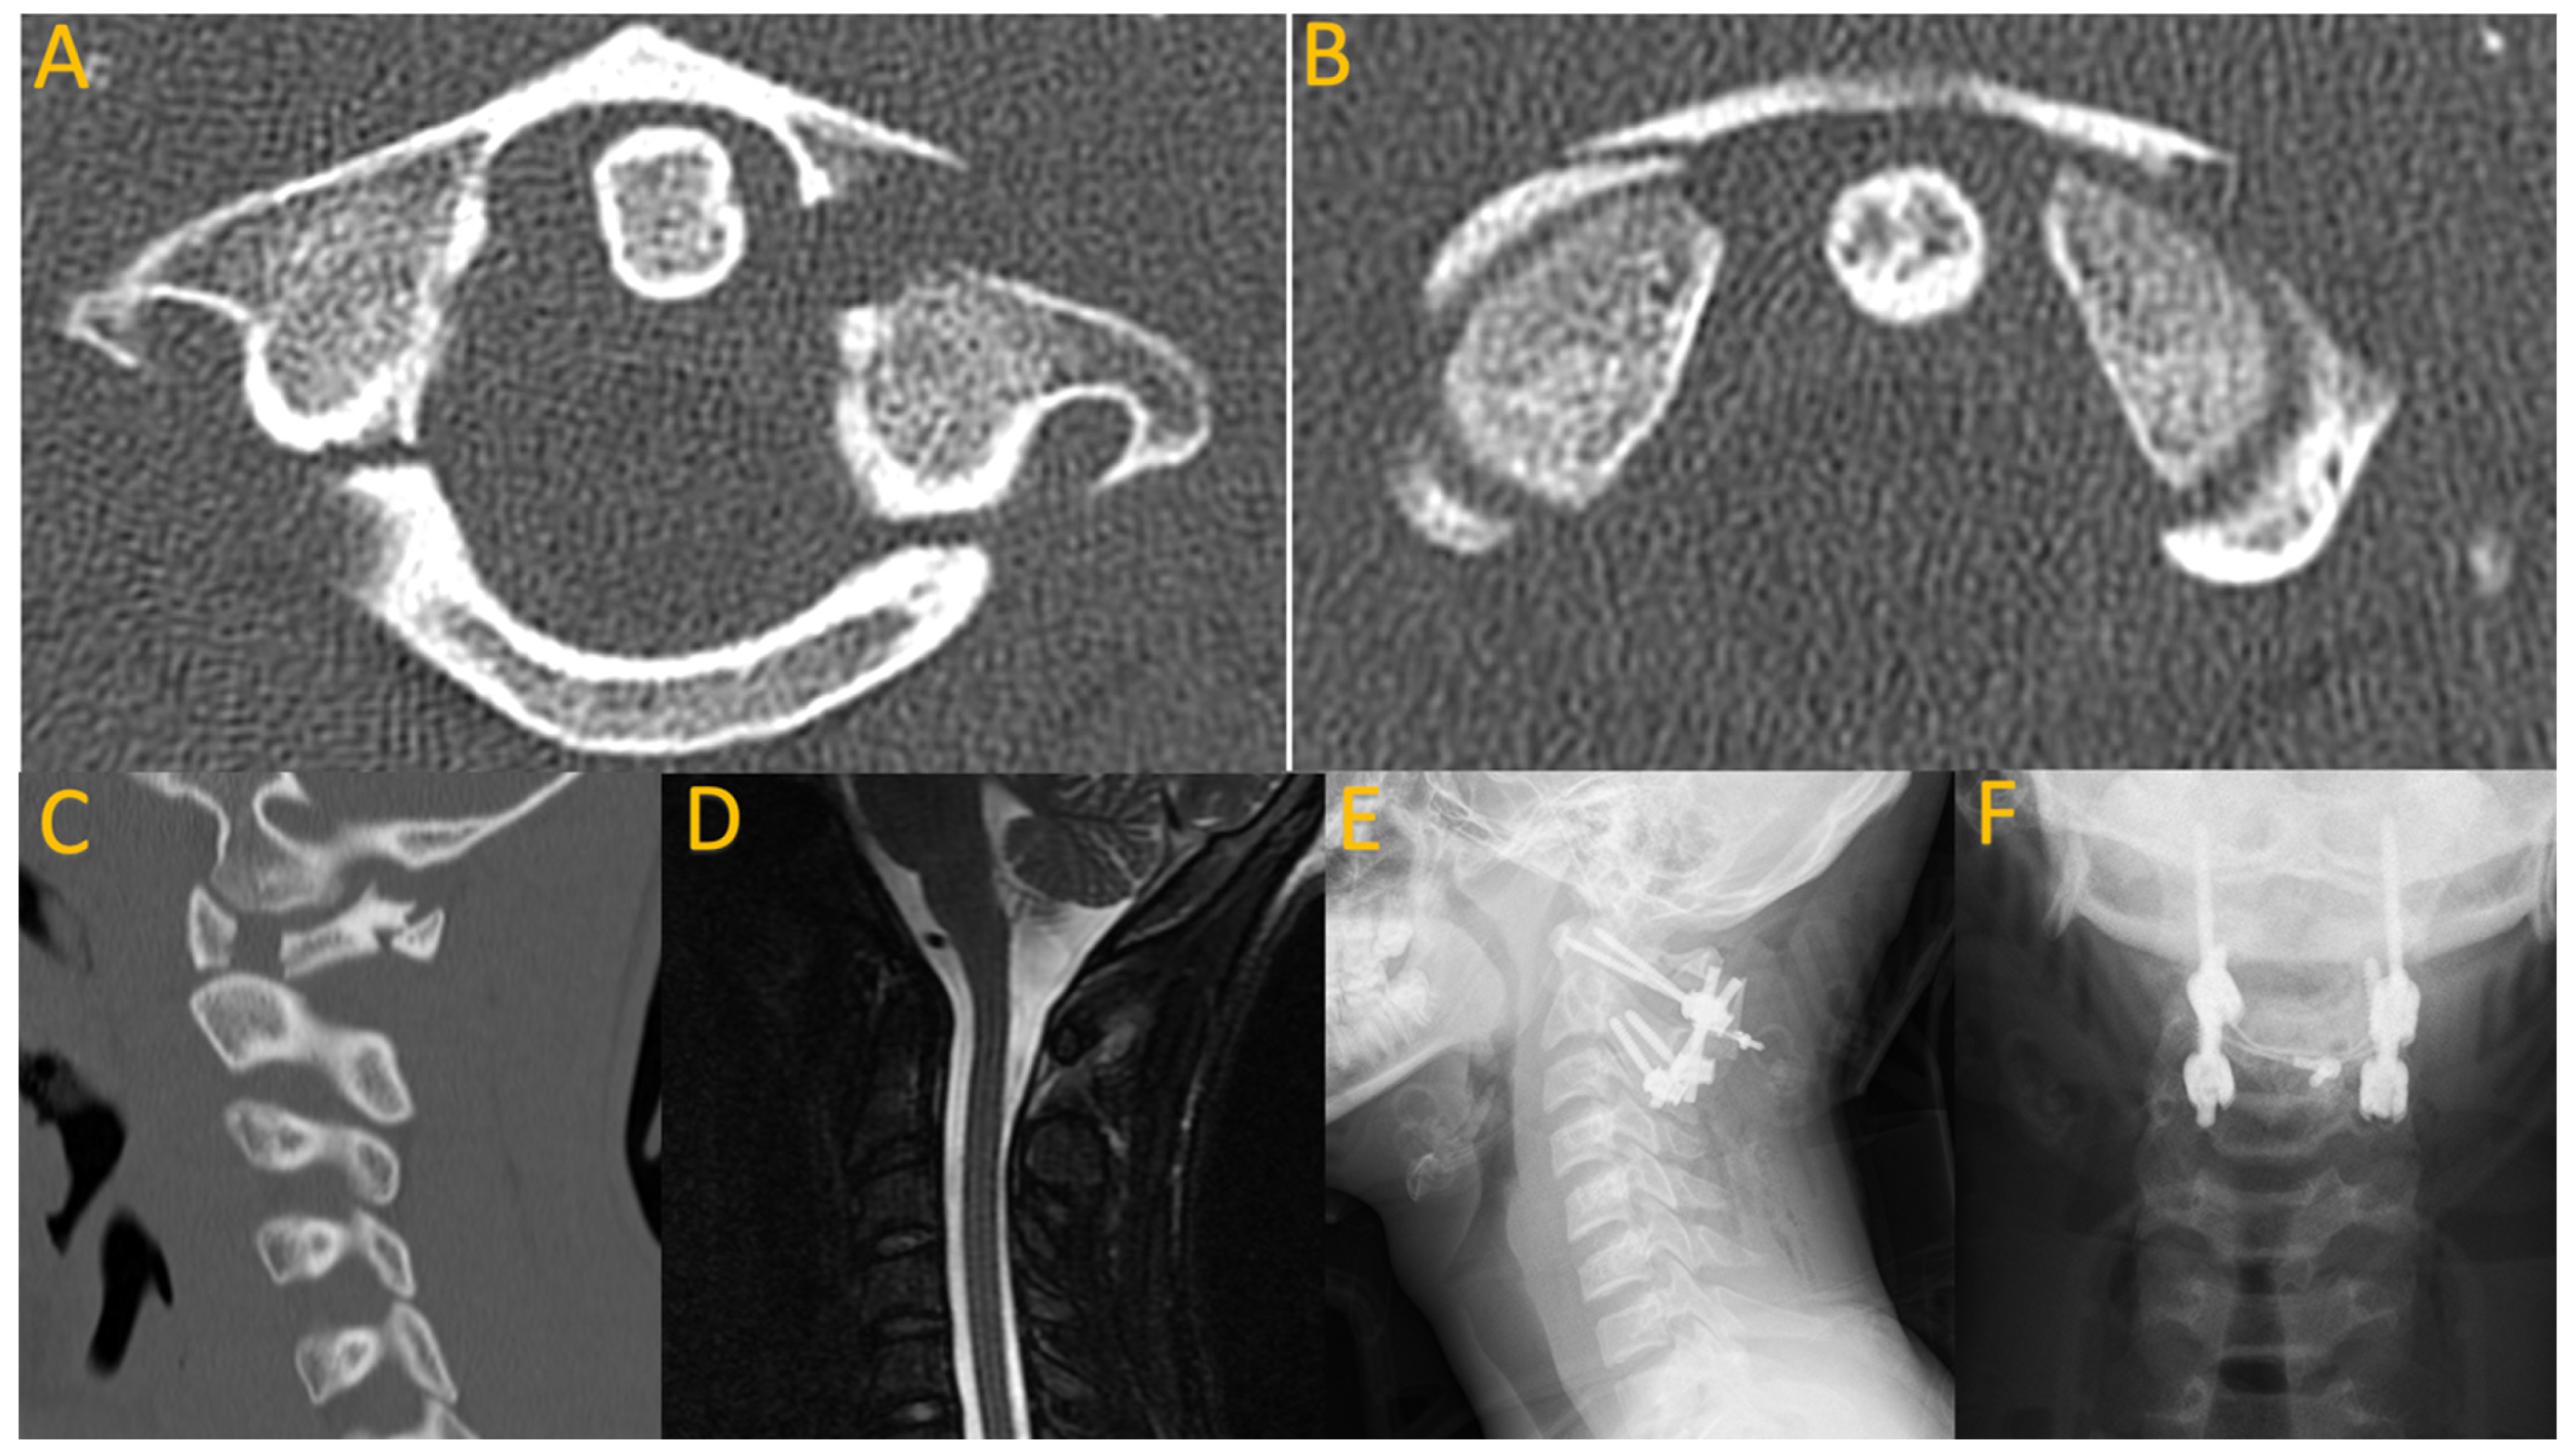

Jefferson fractures commonly result from falls and motor vehicle accidents, and involve a four-part burst fracture of C1. They are rarely seen in young children given incomplete ossification and presence of cartilage helping to decrease overall transmitted force [18]. Jefferson fractures may be associated with injury of the transverse ligament and/or associated C2 fracture. Diagnosis can be made using plain radiographs or CT; transverse ligament integrity can be assessed utilizing the Rule of Spence (sum of overhang of bilateral C1 lateral masses on C2 lateral masses > 7 mm) as well as MRI. Treatment typically involves external immobilization as long as the transverse ligament remains intact, with halo immobilization or C1–2 instrumentation and fusion if ligamentous instability exists (Figure 1) [19].

Figure 1.

A 16-year-old male who presented with neck pain after diving into shallow water in the ocean, hitting a sand bar. He was neurologically intact. Axial (A,B) and sagittal (C) CT imaging reveals a four-part burst fracture of C1. Sagittal MRI STIR sequence suggests ligamentous injury (D). He underwent posterior C1–C2 fusion with instrumentation, wiring, and allograft (E,F).